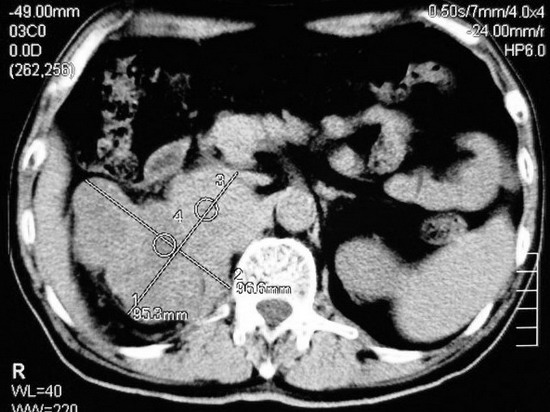

以下是引用杀毒软件在2008-11-17 19:15:00的发言:[br]考虑------右肾癌合并肾静脉---同侧肾上腺受侵可能性大

以下是引用zjzjr在2008-11-17 20:45:00的发言:[br]考虑------右肾癌合并肾静脉---同侧肾上腺受侵可能性大及腹膜后淋巴结转移.